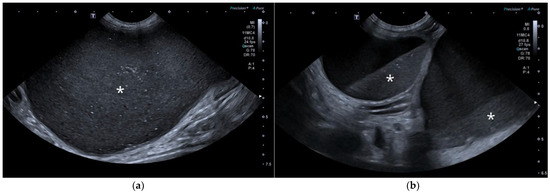

Uterus masculinus is a rare disorder of sexual development in males, characterized by the presence of tubular female genitalia. Diagnostic imaging reports of infected uterus masculinus are limited. We describe the ultrasonographic and computed tomographic findings in three dogs, all presenting with abdominal distension, pain, and systemic infection. Imaging consistently revealed a fluid-filled, bicornuate structure arising from the prostate. In two dogs, the horns extended through the inguinal rings to the scrotal testes; in the third, with a prior left orchiectomy, both horns were intra-abdominal, the right ending in a peritoneal mass. Surgery and histopathology confirmed infected uterus masculinus, with Escherichia coli isolated from urine in all dogs and from the structure in two. Two dogs had Leydig cell tumors, one with concurrent uterine neoplasia; the third had an ovarian or ovotesticular granulosa cell tumor. Although rare, infected uterus masculinus is potentially life-threatening and should be considered in male dogs with abdominal pain, distension, or systemic infection. This is the first case series describing combined ultrasonographic and tomographic features of infected uterus masculinus, including novel findings such as cervix-like mural narrowing and fluid–fluid levels. It is also the first imaging description of an ovarian or ovotesticular tumor in a dog with uterus masculinus. Full article

Figure 1